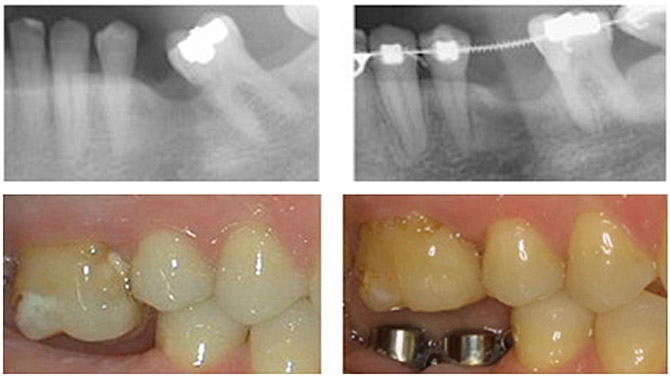

Los registros diagnósticos (fotografías, radiografías y estudio de modelos) determinarán el tratamiento ortodóncico apropiado, que puede ser completo en ambas arcadas o parcial, solo en parte de una arcada.

Los motivos por los que puede ser necesario recurrir al tratamiento de ortodoncia antes de la colocación de un implante pueden ser los siguientes:

- Que el diente o dientes adyacentes al espacio edéntulo se hayan inclinado, provocando una falta de espacio que impide o dificulta el acceso para la colocación del implante.

- Que el diente antagonista, es decir, el diente de la arcada contraria, se haya desplazado en sentido vertical debido a su anoclusión (ausencia de contacto).

- Que se den ambas circunstancias.

- Que sea necesario crear un nivel óseo adecuado: Ciertos movimientos dentarios inducidos por el tratamiento de ortodoncia favorecen la formación de tejido óseo y/o gingival, es decir, hueso y encía.

- Además, en ciertos casos severos de inclinación puede ser necesaria la colocación de microimplantes, que son pequeños 'tornillos' que se anclan en el hueso y sirven de apoyo para poder enderezar las piezas dentales.

En este tipo de tratamientos multidisciplinares, es muy importante la colaboración conjunta de ambos profesionales, ortodoncista e implantólogo. Tras estudiar en conjunto el problema del paciente, se decidirá si requiere un tratamiento ortodóncico para preparar el espacio antes de colocar el implante, puesto que una vez colocado se limitan los movimientos de los dientes adyacentes.